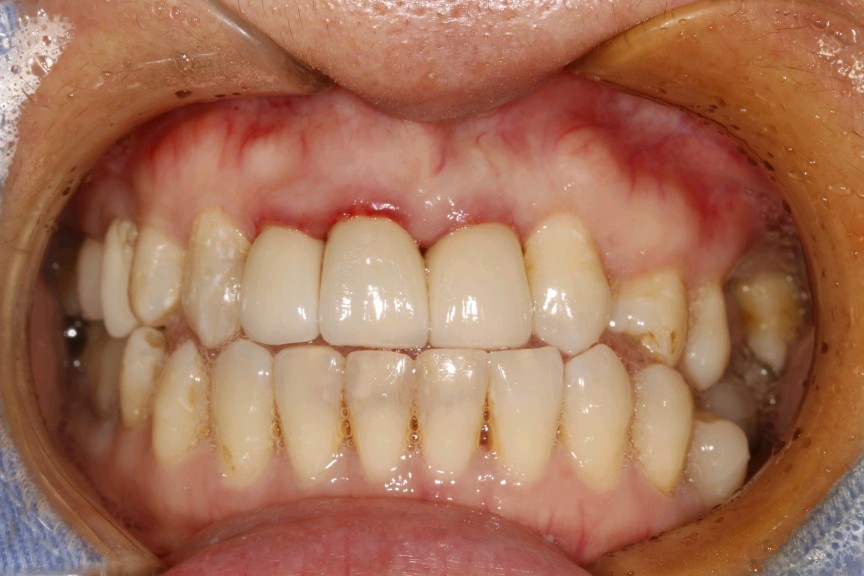

患者女,三十岁,11、12、21牙已行根管治疗,11、21烤瓷全冠修复。由于长时间烤瓷牙的佩戴,导致牙龈边缘发黑,颈缘处牙龈组织出现"黑线"。腭侧部分也出现了崩瓷的现象。对于这种情况,建议患者尽早重新修复,避免二次伤害。患者最终选择重新修复,也给出患者合理的方案,患者选全瓷冠修复,与今日佩戴完毕。边缘密合度良好,形态色泽自然美观,患者满意。

术前

术后